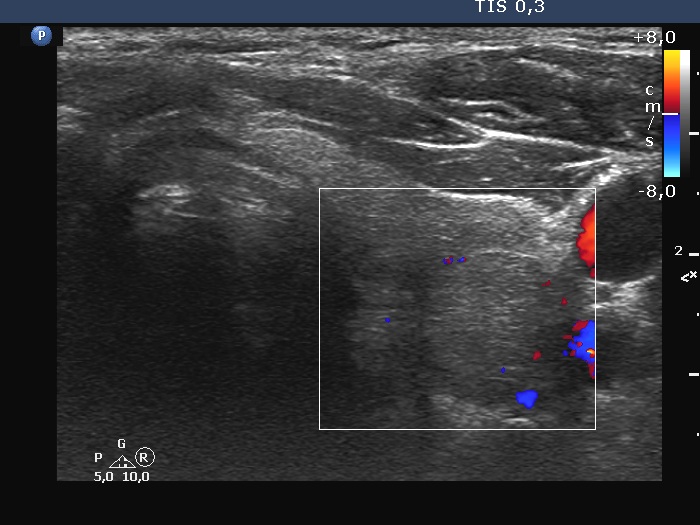

Right lobe, longitudinal scan

Left lobe, transverse scan, color Doppler mode. The vascularity is very scanty.